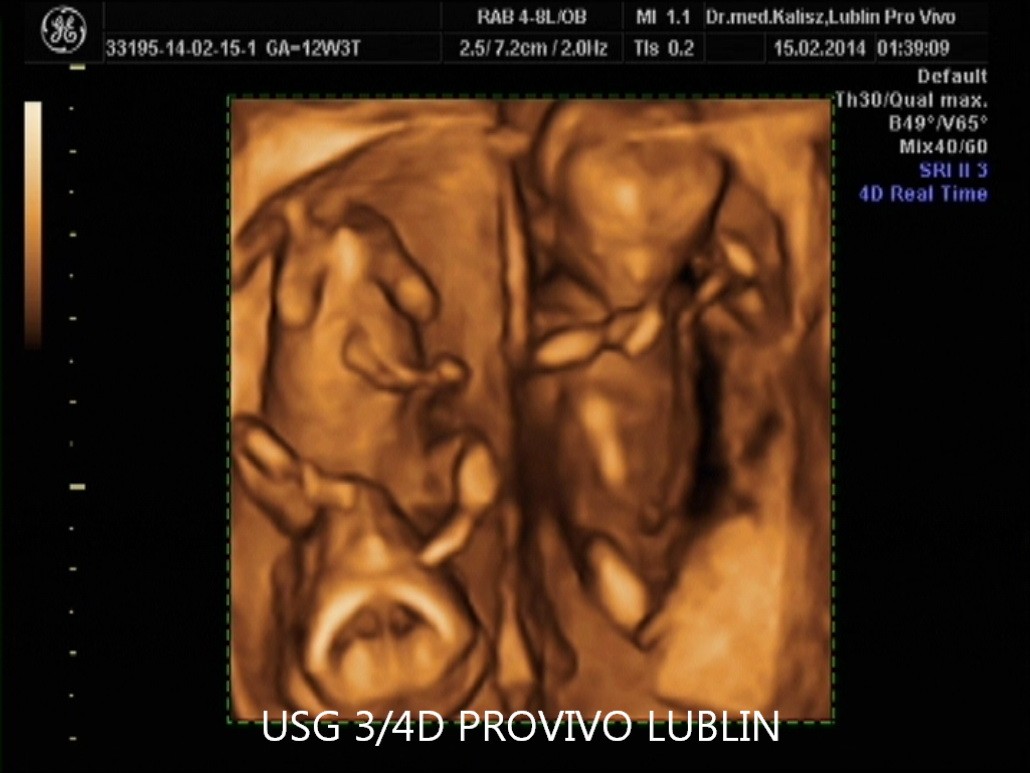

BADANIE USG 3/4D umożliwa dokładny wgląd w rozwój płodu, pozwala na podglądnięcie dziecka w sposób niemalże identyczny z jego aktualnym wyglądem.

W trakcie trwania badania obraz rejestrowany jest na płycie DVD, tak aby każdy przyszły rodzic mógł ponownie odtworzyć badanie w domowym zaciszu. Podczas badania płodu USG 3/4D istnieje również możliwość wydruku zdjęć w formacie kartki pocztowej(148 × 100 mm). Doskonałą jakość, którą charakteryzują się wykonywane przez nas odbitki cyfrowe uzyskujemy dzięki używaniu wyłącznie markowych papierów fotograficznych.